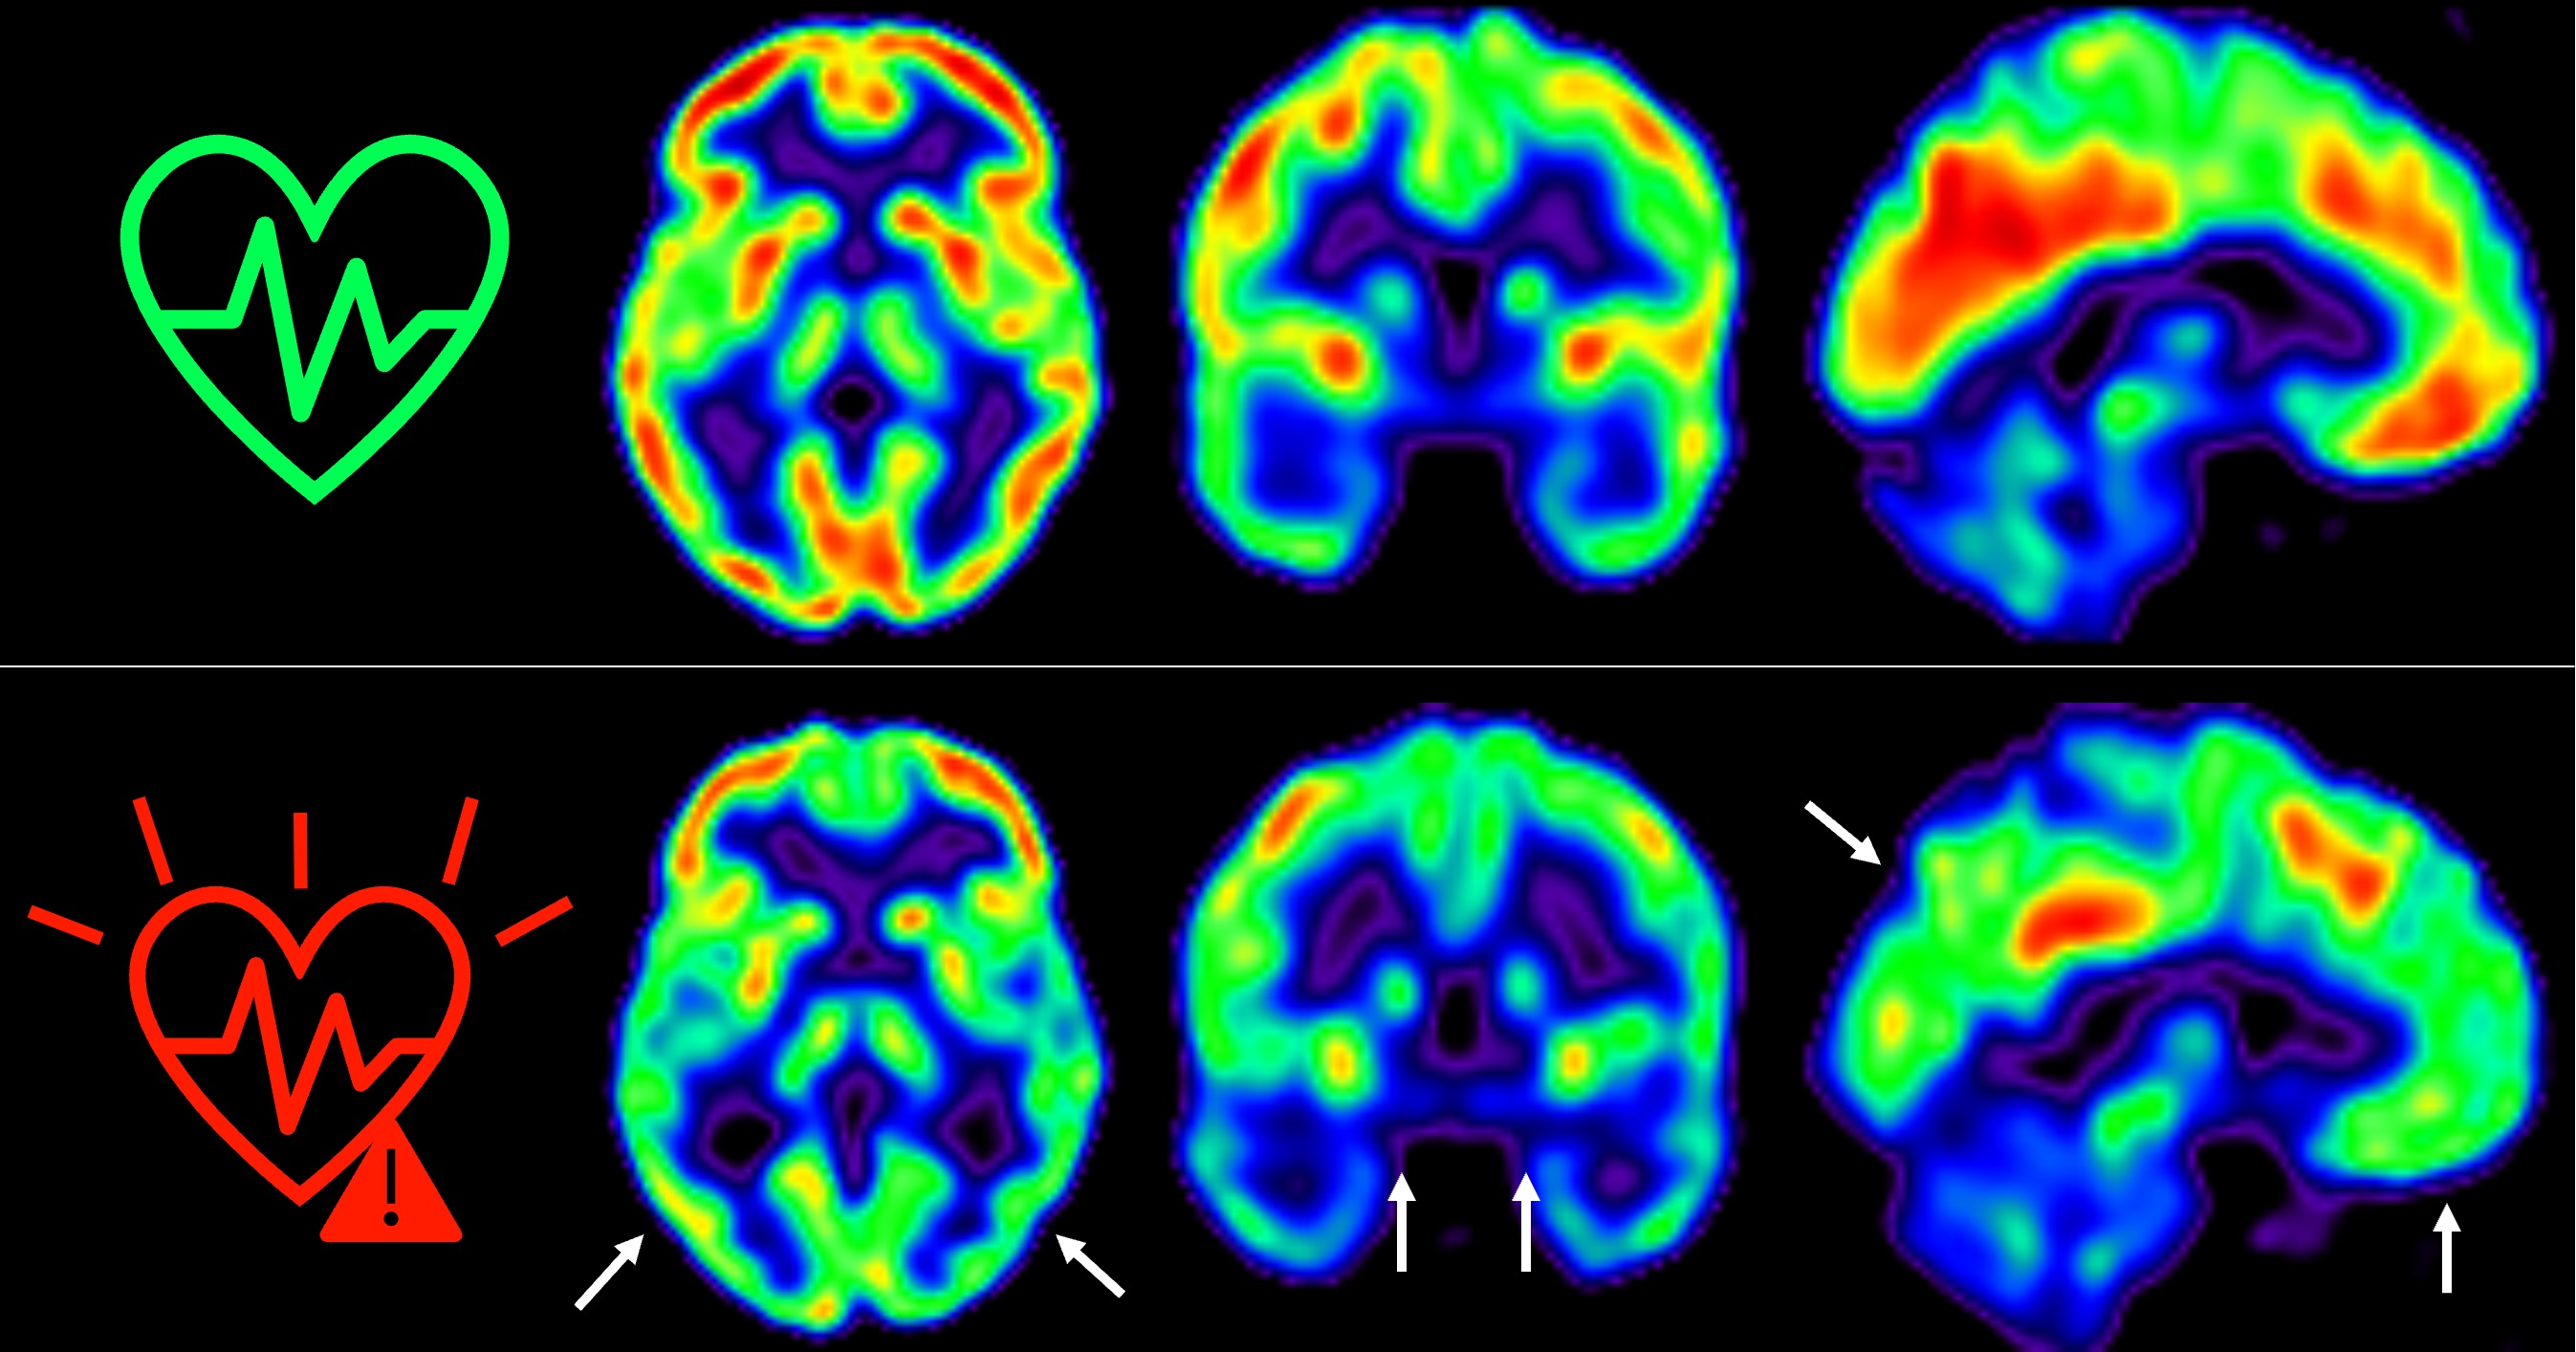

Descubren que existe una relación entre la grasa y la función cognitiva del cerebro

29/09/2023